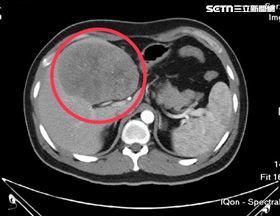

33歲男解黑便吐血 醫一看11cm嘆晚期了

33歲吳先生去年因解黑便及吐血就醫,確診胃癌並肝轉移...